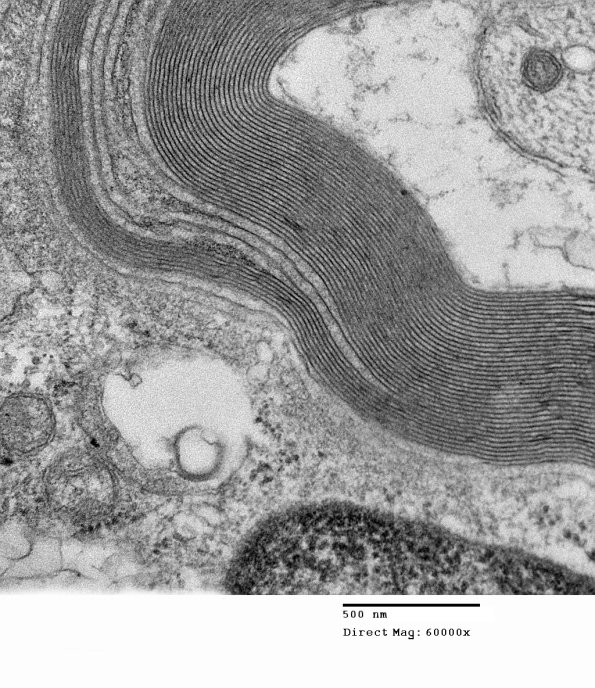

Although the outermost lamellae are preferentially involved, the pattern often varies. (electron micrographs)